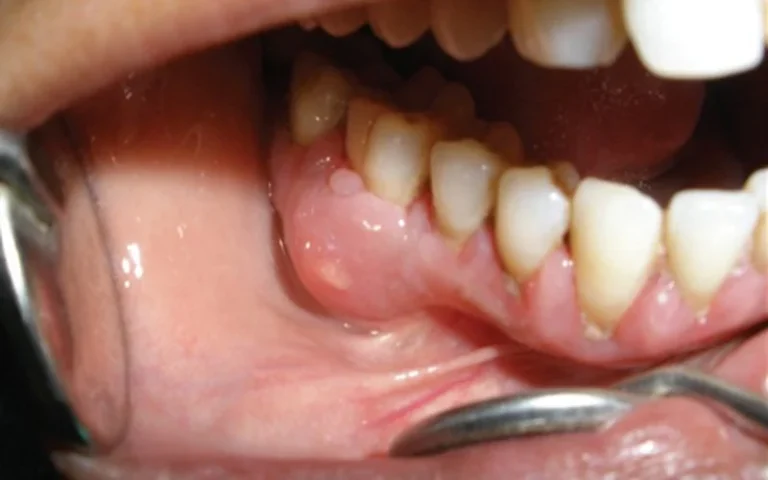

ÁP XE RĂNG – NGUYÊN NHÂN, TRIỆU CHỨNG VÀ CÁCH ĐIỀU TRỊ

Áp xe răng là một bệnh lý nha khoa do vi khuẩn gây nên, khiến cho răng bị nhiễm trùng và hình thành các túi mủ dưới vùng chân răng. Bệnh áp xe răng không...